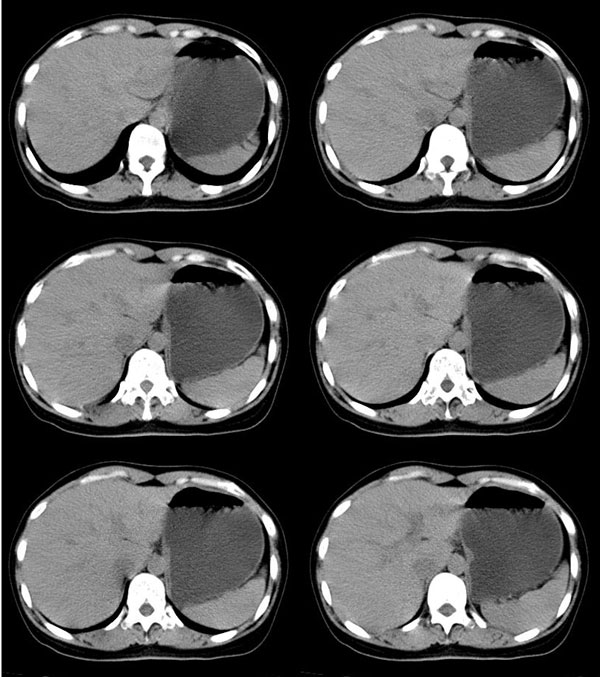

以下是引用guzhongliangddd在2006-11-9 17:55:00的发言:[br]请重点讨论图中箭头所示{脾门部,我首先考虑的是1:血管结构2:胰尾组织??)[br][br][本贴已被 guzhongliangddd 于 2006-11-9 18:01:50 修改过]

以下是引用西北偏北在2006-11-9 20:15:00的发言:[br]箭头所指结构边缘不光整,不支持副脾,考虑胰尾容积层面或血管,做个增强吧.